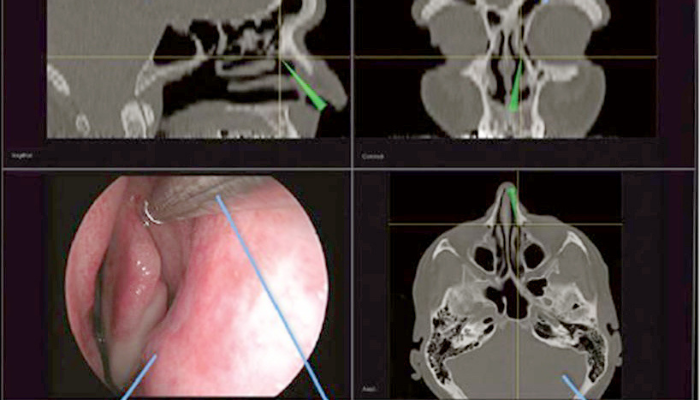

Surgical Navigation

The system supports classic navigated surgical interventions:

- Chronic sinusitis

- Removal of nasal polyps

- Frontal sinusotomy

- Surgery in unusual sinus anatomy

- Partial removal of the medial orbital wall

- Resection of ethmoidal cells and the sphenoid

The Navigation System can be easily integrated into any endoscopy tower or any microscope.

The system enables simple and fast patient registration.

Due to its excellent compatibility, navigation can be performed using CT, MRI or DVT images.